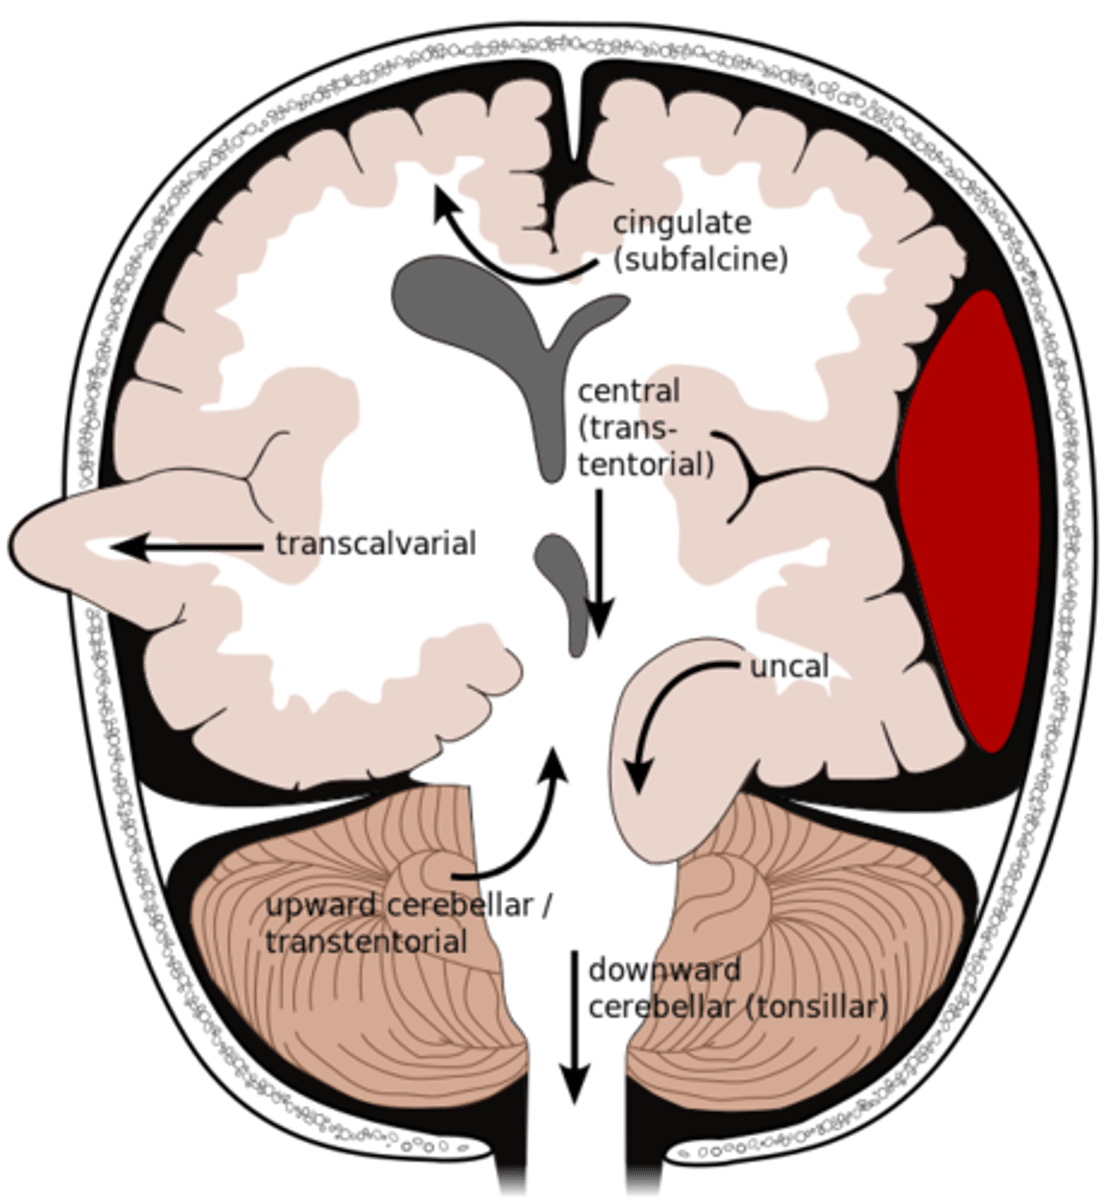

What is an uncal herniation?

most common.

unilateral lesions forces uncus of temporal lobe to displace and compress on the midbrain.

What is a central herniation?

Downward shift of cerebral hemisphere, compressing the brainstem

What is a cingulate herniation?

shift of brain tissue from one hemisphere to the other. Compress anterior cerebral artery.

Ischemic stroke may occur

What is a transcalvarian herniation?

brain begins to herniate outside of the skull. the brain will squeeze out of fractures, burr holes, or surgical incisions.

What is an upward herniation?

displacement of the cerebellum upward

What is a cerebellar Tonsillar herniation?

displacement of cerebellar tonsils downward this compressing the pons/medulla

s/s: alterations in resp. and cardiac functions- rapidly progressing to cardiac arrest, Headache and neck stiffness, reduced muscle tone